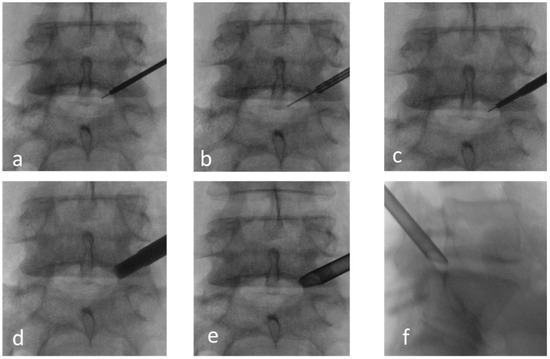

3.3. Clinical Case 1